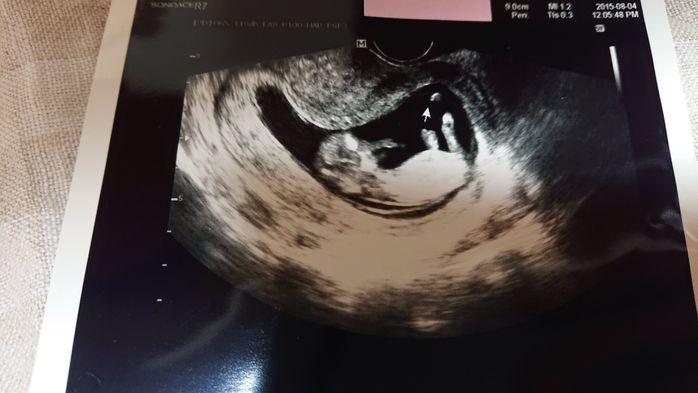

《妊娠7週目のエコー写真》

妊娠7週目の健診日には、午前中に夫と一緒に市役所へ婚姻届けを提出し、母子手帳も発行してもらいました。夫は車酔いをして具合が悪くなってしまったので、健診の時は夫には留守番をしてもらい、もらいたてホヤホヤの母子手帳を手に、1人でドキドキしながら産婦人科へ行きました。すると、胎嚢の中に赤ちゃんの姿が…!「やっと会えたね~」と、嬉しすぎて食い入るように見ていたエコーの画面。「もっともっと長く見ていたい」と切に願ったほど感激しました。そして、この日は同時に心拍も確認でき、心臓も元気に動いていました。2枚目のエコー写真の右側半分が、心拍を確認できた証拠です。医師からは「小さすぎて予定日はまだ決められないな~。でも、3月上旬ぐらいになるかな~」と伝えられ、予定日確定は次回持ち越しに。夫は「成長遅いんじゃない?」と心配そうにしていました。翌日には、私たちの結婚式が控えていました。その前に赤ちゃんの姿を見つけることができたおかげで、遠方の両親にも直接妊娠報告することができて嬉しかったです。